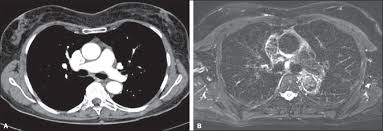

Em TC:

- TC de Tórax com baixa dose (COVID ou nódulos)

- TC de Abdome com protocolo fase única em trauma